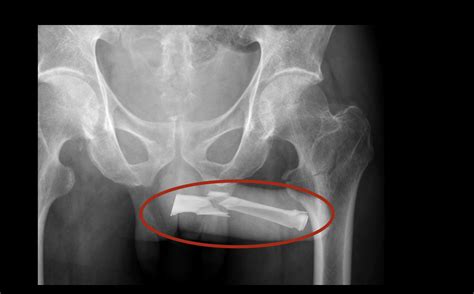

• Injuries: Trauma to the penis, such as from an accident or rough sexual activity, can result in pain. This can include fractures, bruises, or cuts.